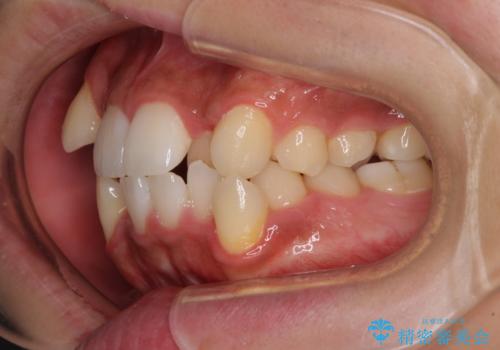

上下の八重歯とクロスバイト ワイヤー装置での抜歯矯正

- 八重歯とクロスバイトを気にして来院された患者様です。

上下ともに八重歯が顕著であり、前歯のクロスバイトがあったため、上下左右の第一小臼歯4本を抜歯し、ワイヤー装置での抜歯矯正を行うこととしました。